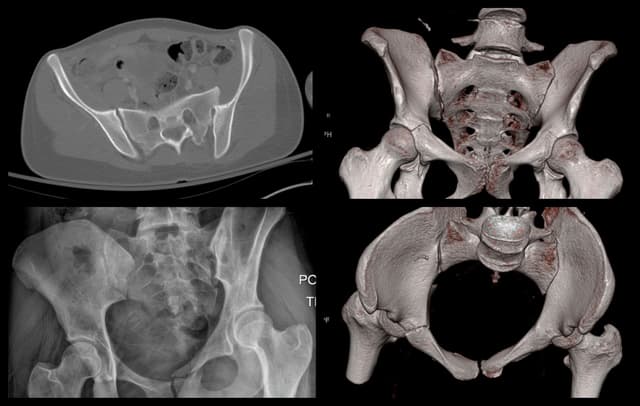

Posterior Sacroiliac Joint Fixation

Imaging

Pre-op

Post-op